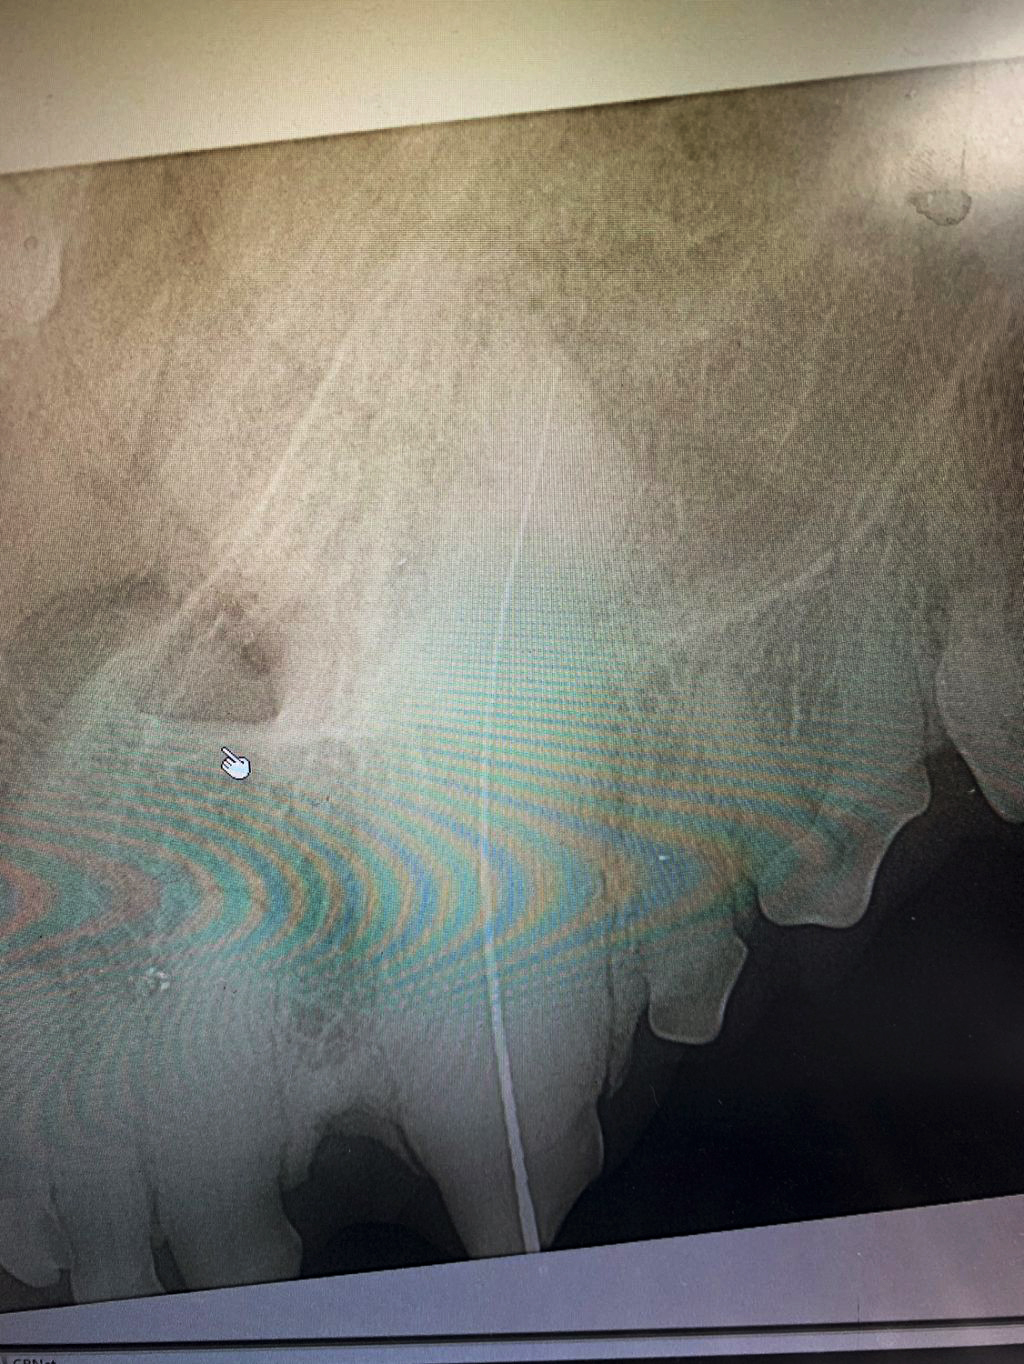

The control X-ray shows the finished Root Canal Fillings on the right and left canine.